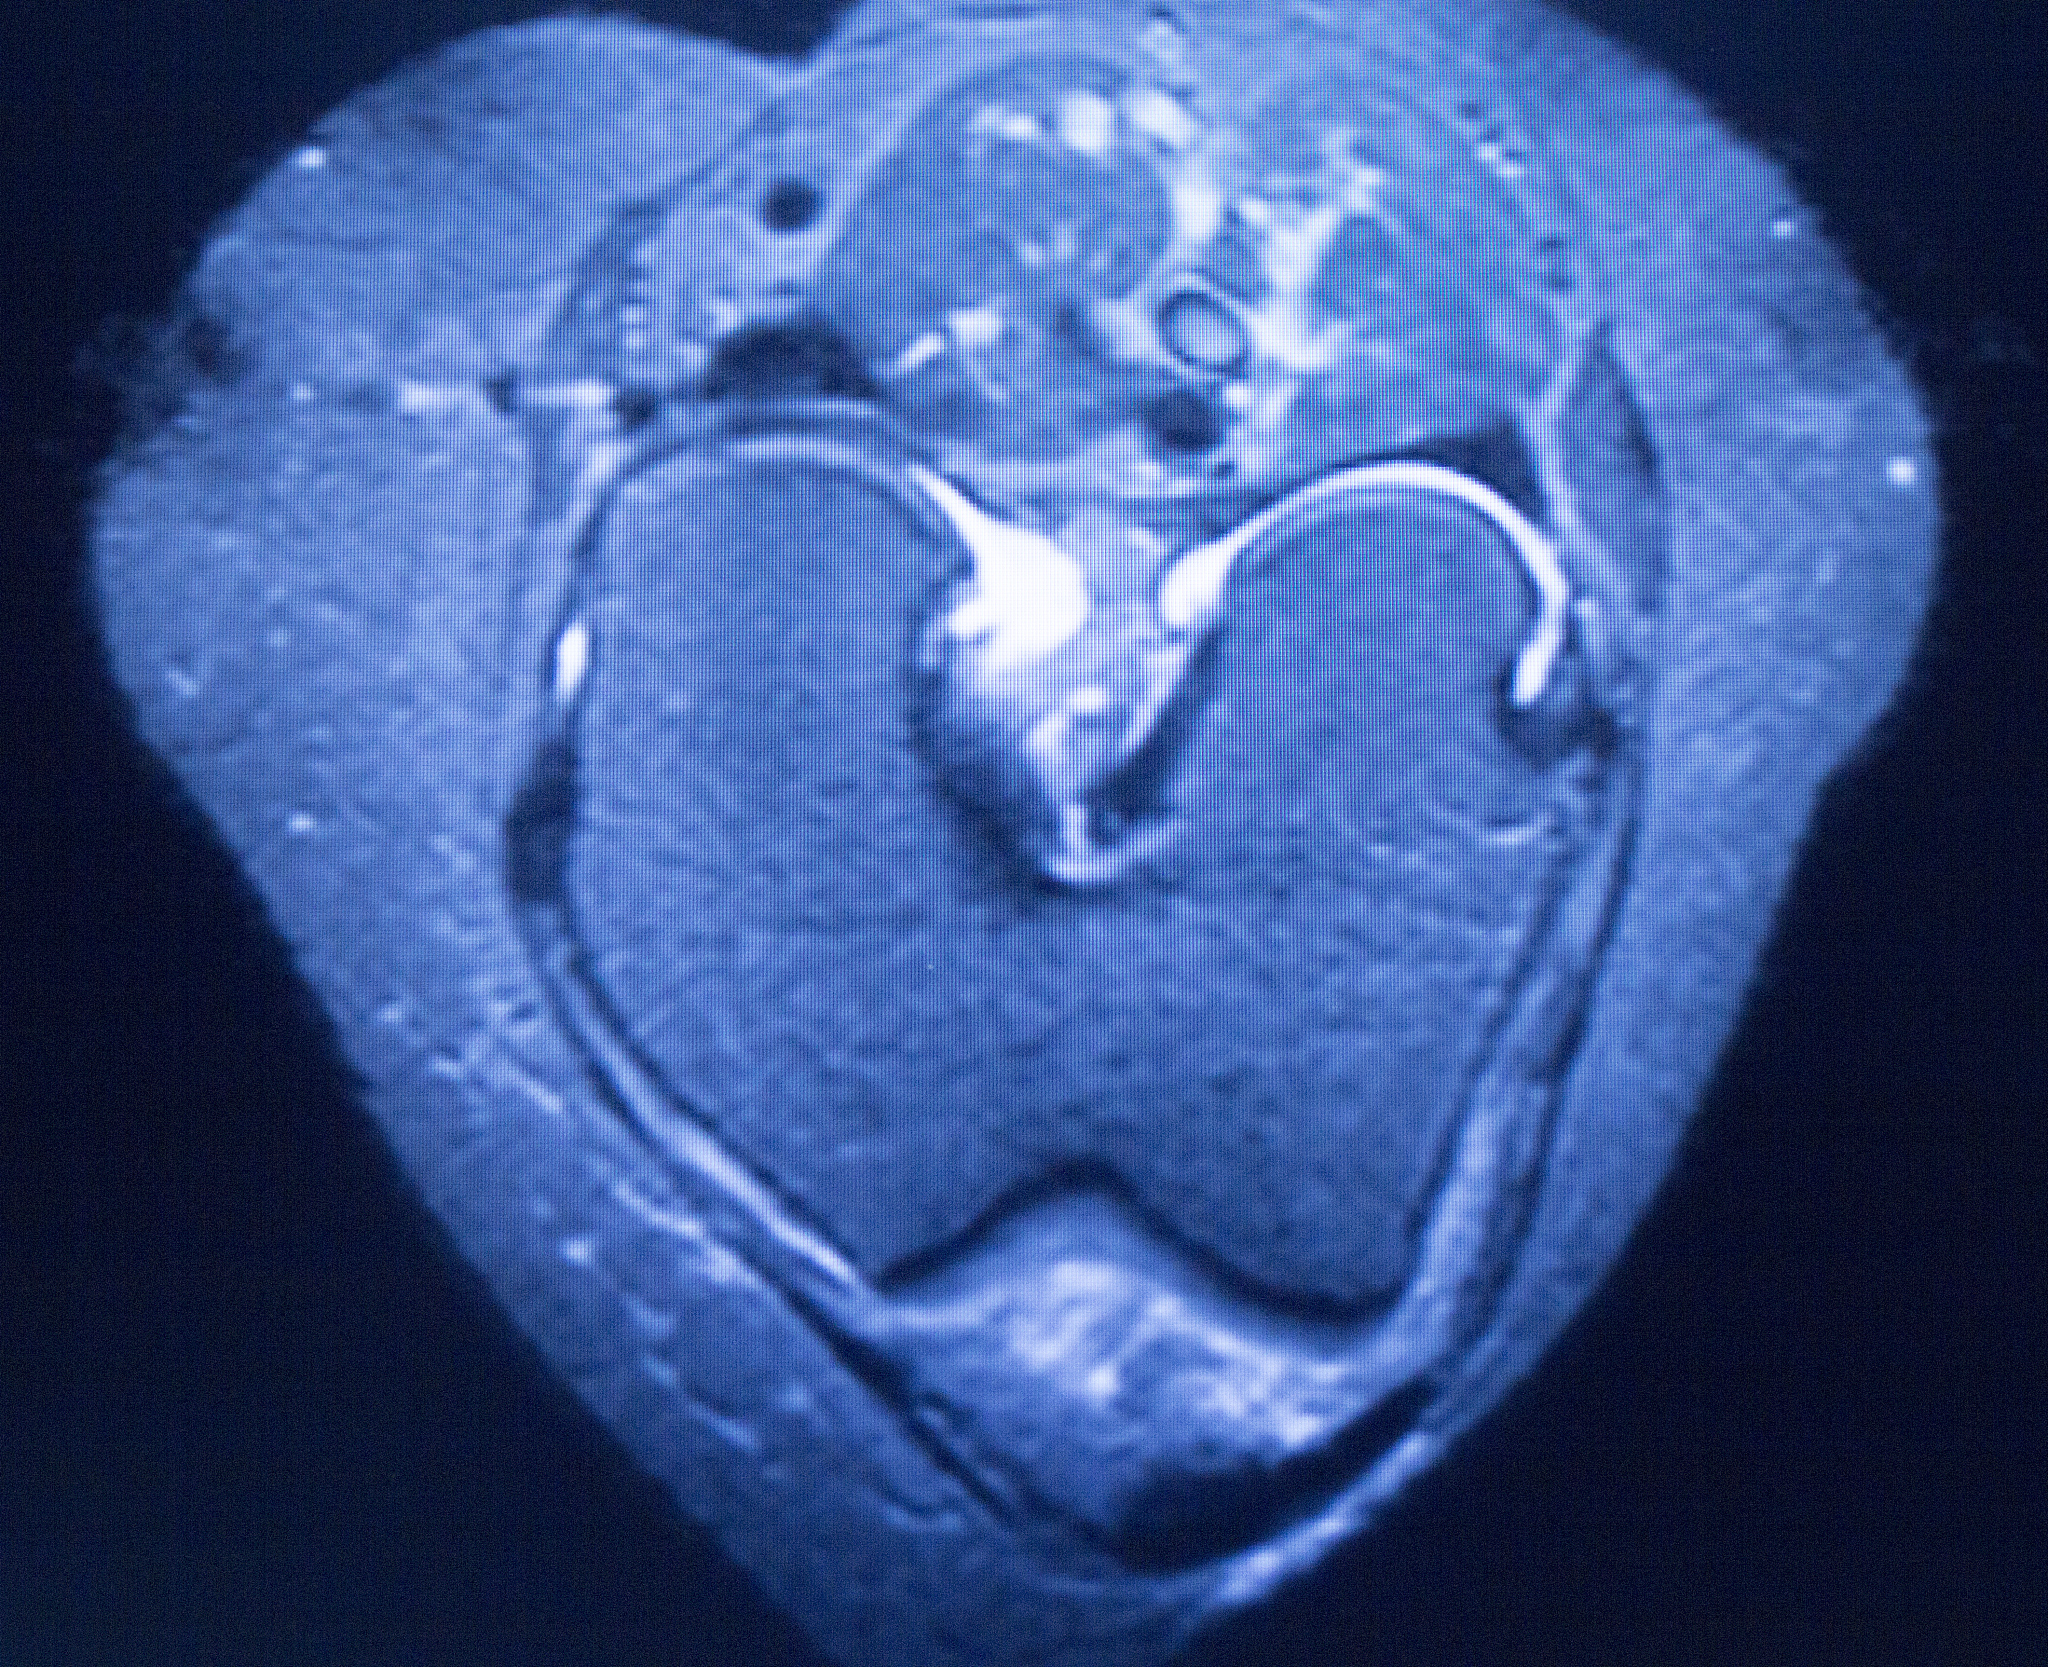

韧带损伤MRI分级(Ⅰ级、Ⅱ级、Ⅲ级)

韧带损伤的磁共振成像 (MRI) 分级是评估韧带损伤严重程度的重要方法。以下介绍三种常见的韧带损伤MRI分级:

• 韧带肿胀较前减轻。* 韧带内高信号较前有所减弱或范围有所缩小,连续性部分仍中断。* 关节腔仍见积液。

Ⅱ级:

• 韧带稍肿胀。* 韧带内高信号较前明显减弱或范围明显缩小,连续性存在。* 关节腔少量积液。

Ⅲ级:

• 韧带基本无肿胀。* 韧带信号正常或仅有轻度不均匀。* 关节腔内无或少量积液。

需要注意的是,这只是一个简单的概述,实际诊断需要结合临床症状和其他影像学检查结果进行综合判断。如有疑问,请咨询专业医生。